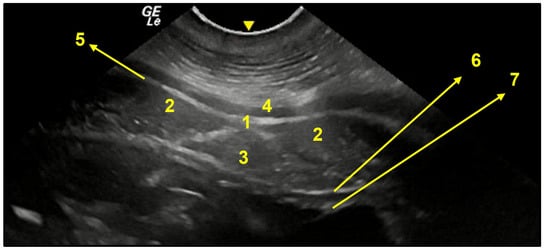

3.3. Ventral Abdominal Ultrasound